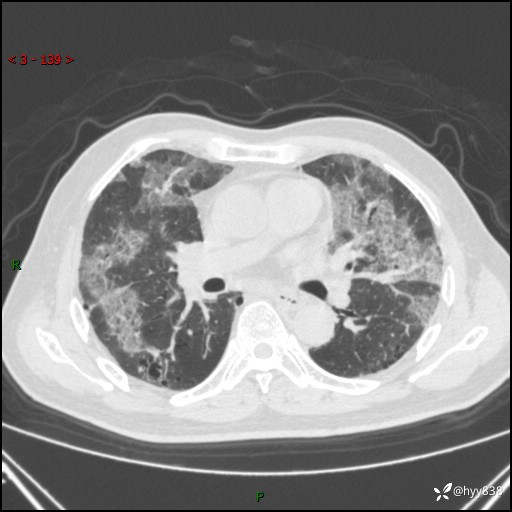

患者性别:男

患者年龄:64岁

简要病史:肝内胆管癌综合治疗后2周余,咳嗽、发热,咳白色泡沫痰。

辅助检查:CT

临床诊断:感染?

讨论:病变性质?